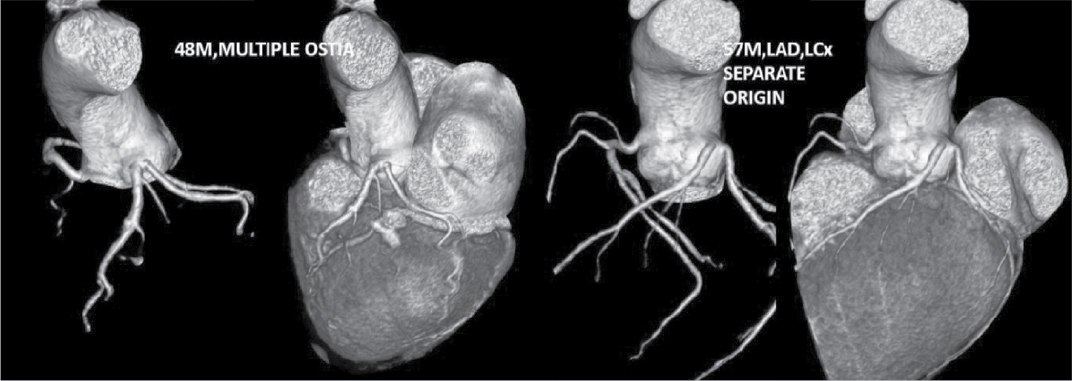

Figure 7. Two patients aged 48/M and 57/M, CT-CAG VRT images showing separate origin of LAD, LCx and there is no LMCA.

At Nizam’s Institute of Medical Sciences (NIMS), Hyderabad, 770 patients underwent CT-conventional coronary angiography (CAG), on 128-slice single source MDCT (SOMATOM Definition AS ± SEIMENS) during the last 3 years (unpublished data). On analysis, coronary artery anomalies were found in 23 patients (3%). Their ages ranged from 25 to 82 years. Majority of the cases were in 51 to 60 years age group. Among them, 17 were males. The most common anomaly seen was high take-off of coronary arteries, seen in 10 cases. Of them, 2 were having high origin of right coronary artery (RCA) (Fig. 1), 7 were having high origin of left main coronary artery (LMCA) and one was having high origin of both coronary arteries with acute kink at the origin of RCA. Anomalous origin of coronary artery from opposite sinus was seen in 8 cases (Figs. 2-5). RCA from left coronary sinus with interarterial course between aorta and right ventricular outflow tract was seen in 5 cases. Anomalous origin of left coronary artery (LCA) from right coronary sinus with interarterial course between aorta and right ventricular outflow tract was seen in 2 cases. Anomalous origin of left circumflex artery (LCx) from right coronary sinus with retroaortic course was seen in 1 case (Fig. 6). Separate ostia for left anterior descending artery (LAD) and LCx was noted in 3 patients (Figs. 7 and 8). Shepherd crook deformity of proximal segment of RCA was seen in 1 patient. Super-dominant RCA with absent LCx was seen in 1 patient (Fig. 9).

Multiple ostia of right and left coronaries can be considered as important anomalies. RCA and conus branch may arise separately. Similarly, LAD and circumflex arise separately with no LCA, which accounts for small percentage with normal course. Incidence of separate ostia for LAD and LCx from left coronary sinus was 0.26% in a series.4 In our series, we had 3 cases of separate origin of LAD and LCx accounting for 0.39%.